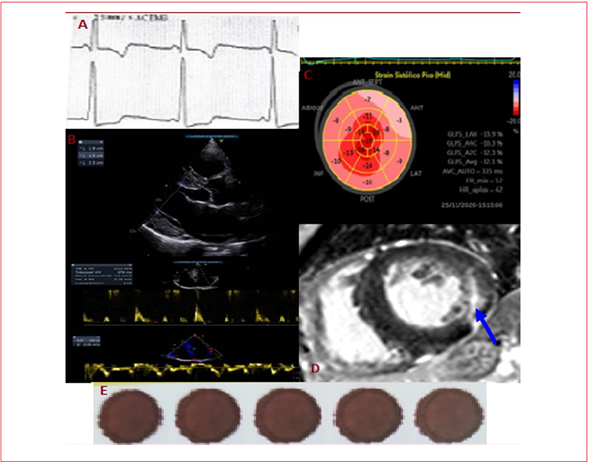

Paciente de sexo masculino, 62 años, trabajador rural. Presenta antecedentes familiares de hermano con enfermedad renal crónica (ERC) y muerte súbita a los 54 años, y madre con cardiopatía no especificada fallecida a los 60 años. Rfiere antecedentes personales ERC diagnosticada hace 9 años. La ecografía renal informa riñones atróficos, no se realizó biopsia diagnóstica. Ingresa a plan de hemodiálisis en junio de 2012 y recibe trasplante renal en octubre de 2012. Desde entonces, se encuentra en tratamiento inmunosupresor y controles periódicos. Se destaca ausencia de hipertensión arterial y de otros factores de riesgo cardiovascular conocidos. En su electrocardiograma presenta criterios de HVI por voltaje y trastornos de sobrecarga sistólica del ventrículo izquierdo. El ecocardiograma transtorácico realizado en 2012 informa HVI concéntrica severa con fracción de eyección del ventrículo izquierdo (FEVI) normal y disfunción diastólica con llenado restrictivo, E/e´ 18. Episodios de dolor torácico atípicos en 2015 motivan centellograma con dipiridamol; este informa HVI severa, lo cual es negativo para isquemia. Reitera dolor torácico sin cambios electrocardiográficos, con troponinas positivas. Se realiza cineangiocoronariografía; esta informa ausencia de lesiones coronarias significativas. Tres años después es enviado desde nefrología a consulta con cardiología por episodios de hipotensión arterial y edemas de miembros inferiores simétricos bilaterales en tratamiento con hidroclorotiazida, sin respuesta a dicho tratamiento. El electrocardiograma muestra ritmo sinusal con intervalo PR de 120 ms, QRS y repolarización sin cambios (figura 1 A). Del resto de la paraclínica destacamos: radiografía sin edema pulmonar, con leve aumento del índice cardiotorácico. El nuevo ecocardiograma transtorácico informa: severa HVI concéntrica, hiperecogenicidad del septum interventricular, FEVI normal, patrón de llenado del VI rígido, aurícula izquierda moderadamente dilatada (figura 1 B), strain longitudinal del VI globalmente disminuido a franco predominio de los segmentos basales y medios, sobre todo lateral basal (figura 1 C). Con la sospecha clínica de miocardiopatía hipertrófica o infiltrativa se solicita resonancia magnética cardíaca que evidencia HVI, FEVI normal y realce tardío positivo intramiocárdico (no isquémico) en los segmentos laterales medio ventricular basal y medio. Se plantea la ausencia de características típicas de miocardiopatía hipertrófica, lo que puede corresponder a patrón de realce evidenciado en enfermedad de Fabry (figura 1 D). Repasando los criterios mayores de enfermedad de Fabry el paciente presentaba HVI concéntrica y ERC que requirió trasplante renal. Al volver a interrogar al paciente, se comprueba historia de acroparestesias y presencia de angioqueratomas en región inguinal. Como criterios menores de la anamnesis y del examen físico, presentaba antecedentes familiares de enfermedad cardíaca y renal. Relata también hipohidrosis, cólicos abdominales, diarreas posprandiales. Los edemas de miembros inferiores son, en realidad, linfoedemas, característicos en esta enfermedad. Se realiza solicitud de actividad de enzimas lisosomales por técnica de gota de sangre seca en papel de filtro (figura 1 E). Esto demostró actividad de GLA deficiente (0,59 μmol/l/h, con valores de referencia 2,1-10,5 μmol/l/h). Como las determinaciones de actividad enzimática son test de screening, ante un resultado patológico se realiza estudio genético (análisis de ADN de leucocitos de sangre periférica). Este estudio informó deleción de 3 pares de bases en exón 7 del gen GLA. Esta mutación ya ha sido descrita en pacientes con enfermedad de Fabry y se considera patogénica( 2). Confirmado el diagnóstico de enfermedad de Fabry en su forma clásica, se asesora al paciente sobre las características de la enfermedad, su tratamiento y se realiza consejo genético para seguimiento de familiares (5 hijas portadoras heterocigóticas actualmente asintomáticas). Se completa valoración con Holter que evidencia ritmo sinusal durante todo el estudio, frecuencia promedio de 70 cpm, PR corto de 111 ms (elemento frecuente de la enfermedad), extrasístoles supraventriculares frecuentes. No presenta arritmias. La valoración por oftalmólogo evidencia vasos irregulares con ectasias en conjuntiva, cataratas discretas, fondo de ojo con vasos tortuosos, córnea verticillata en estudio de lámpara de hendidura (criterio menor enfermedad de Fabry) 1. Se realiza audiograma, en el que se presenta disminución de audición-presbiacusia (criterio menor de Fabry1). Se solicita TAC de cráneo que informa calcificaciones en núcleos lenticulares, tálamo y cerebelo, habituales en la enfermedad de Fabry2. Además, lesión hipodensa parasagital y frontal izquierda (criterio menor de alteraciones vasculares en TAC). La RNM presenta calcificaciones en núcleos dentados del cerebelo y en núcleos grises de la base (habituales en esta enfermedad). En la tabla 1 se repasan los criterios mayores y menores presentes en el paciente. Respecto al tratamiento de reemplazo enzimático, disponemos de tratamiento con alfagalactosidasa A recombinante, un tratamiento muy efectivo de alto costo. Para que el Fondo Nacional de Recursos otorgue cobertura es necesario cumplir con criterios de inclusión y exclusión específicos3. El paciente realiza infusiones intravenosas cada 2 semanas con alfagalactosidasa A (tratamiento crónico con dosis de 0,2 mg/kg en adultos). No presentó efectos secundarios relevantes, salvo hipotensión transitoria que respondió a aporte de volumen intravenoso y enlentecimiento de infusión. Posteriormente, tuvo buena evolución clínica, se constató disminución de acroparestesias y desaparición de linfoedemas.

Figura 1 Estudios realizados. A) Parte de trazado electrocardiográfico (DI), ritmo sinusal con intervalo PR corto de 120 ms, característico de la enfermedad de Fabry4, HVI con alteración de la repolarización secundaria a sobrecarga sistólica. B) ETT demostró una miocardiopatía hipertrófica simétrica no obstructiva en reposo ni dinámica; espesor máximo de la pared septal de 23 mm. Esto es habitual en la enfermedad de Fabry, por lo que puede ser un punto diferencial con la MCH, aunque también existen variantes asimétricas y apicales en casos minoritarios5. Disfunción diastólica severa con patrón de llenado restrictivo (E/e´ 16) característico de las miocardiopatías restrictivas. C) Strain longitudinal global disminuido de -13,9%, afecta segmentos basales a predominio anterior en este caso. La fracción de eyección del VI se encuentra conservada hasta etapas tardías en el Fabry, el deterioro en la deformación longitudinal es más precoz1. D) La resonancia magnética cardíaca demostró realce tardío de gadolinio intramural en la pared lateral basal (flecha azul). Esto concuerda con el fenotipo más frecuente en el Fabry que implica HVI concéntrica y fibrosis miocárdica localizada de forma más predominante en la región inferior o inferolateral basal a nivel intramural6. E) Técnica de gota de sangre seca en papel de filtro (toma correcta de muestra) para medición de actividad alfagalactosidasa A. Actualmente contamos con test de gota seca de sangre periférica que permite estudio enzimático y genético1.